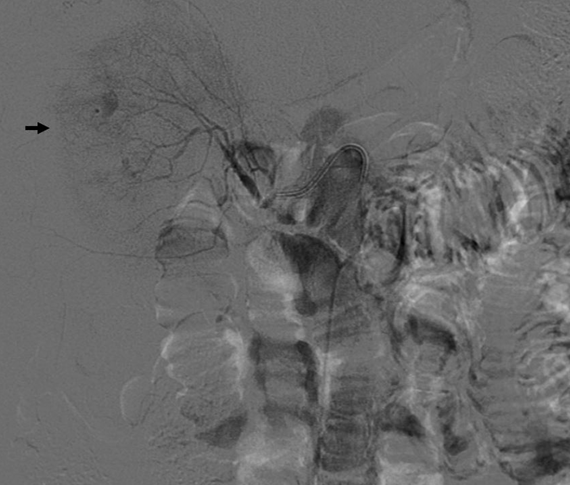

A 48-year-old African-American male with end stage renal disease (ESRD) on hemodialysis for 14 years developed acute abdominal pain during his outpatient dialysis session and was sent to the emergency room. The patient was found to be hypotensive with a blood pressure of 93/72 mmHg requiring fluid resuscitation, which later deteriorated further requiring vasopressors. He was found to have acute anemia with a hemoglobin level of 7.5 g/dL. Abdominal computed tomography (CT) scan revealed large hemoperitoneum with a right perinephric sentinel clot, bilateral multiple renal cysts and features suspicious of bleeding originating from the upper anterior pole of right kidney (Figure 1). The largest of the cysts measured ~3.2 cm in diameter. Renal angiogram showed active ongoing extravasation from multiple branches of the right renal artery (Figure 2). Selective right renal artery embolization was unsuccessful. An emergent laparotomy revealed a torn right renal capsule with subcapsular hemorrhage and a 1.4 cm ragged defect in the inferior portion of the kidney. He underwent right nephrectomy and pathology was negative for malignancy. It essentially showed end stage kidney with arteriolonephrosclerosis, tubular atrophy, interstitial fibrosis, thyroidization, cysts and chronic interstitial inflammation with associated intra-parenchymal and perirenal hemorrhage. Patient refused blood transfusion because of religious reasons and unfortunately died of hemorrhagic shock after the surgery. | ||||||